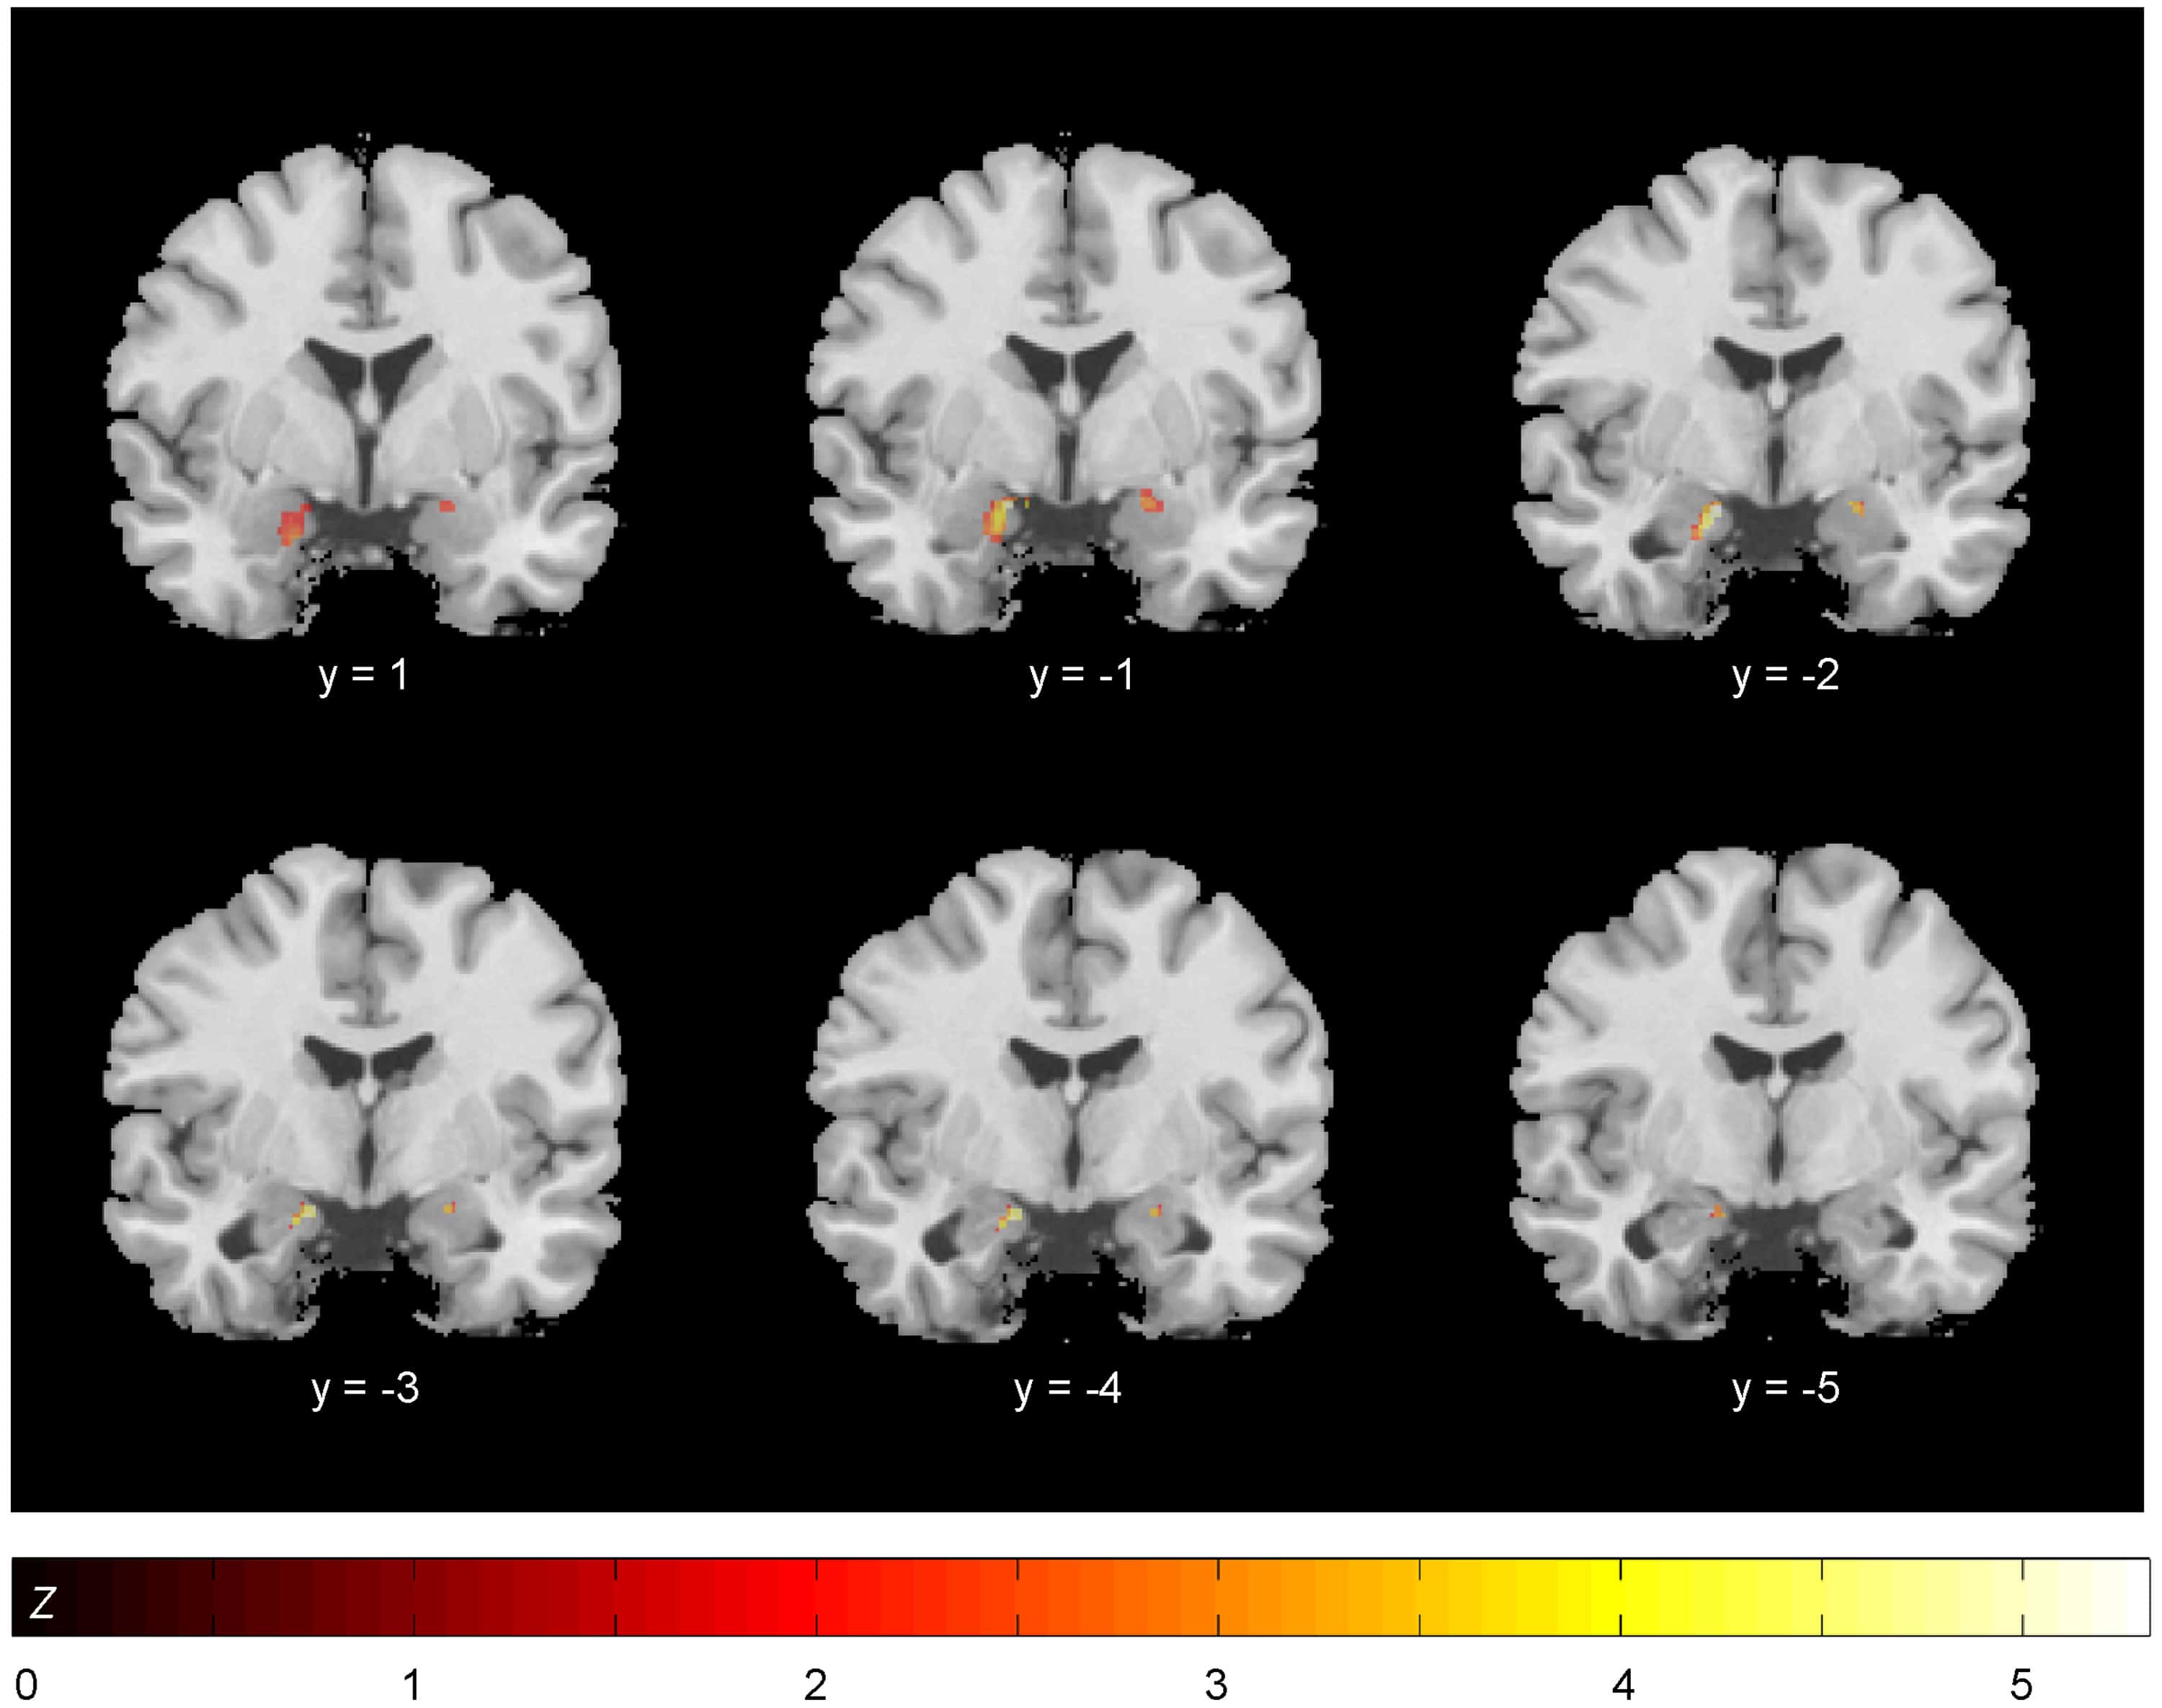

Neuroplasticity in Response to Cognitive Behavior Therapy for Social Anxiety Disorder

Patients with anxiety disorders are characterized by excessive neural reactivity in the amygdala, which is normalized by effective treatment like cognitive behavior therapy (CBT). Mechanisms underlying the brain’s adaptation to anxiolytic treatments are likely related both to structural plasticity and functional response alterations, but multimodal neuroimaging studies addressing structure-function interactions are currently missing. Methods We … Läs mer!